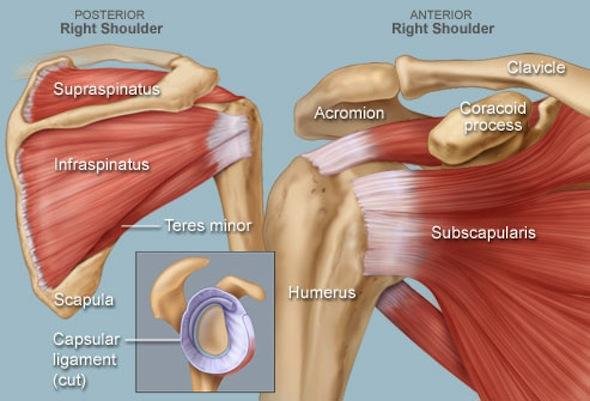

Testing reveals severe range of motion restriction in all directions, notably forward flexion, abduction, and external rotation (the most limited plane). A key differentiator is that both active and passive ROM are limited, tracking a strict 'capsular pattern' with a smooth, solid 'hard stop' at end range, completely free of crepitus or grinding.

Post-Injury Immobilization

Prolonged shoulder immobility acts as a major mechanical pathway trigger. Whether recovering from a rotator cuff tear repair, a stroke-induced hemiplegia profile, or undergoing extended sling dependency, joint disuse sparks an aggressive localized inflammatory cascade that quickly thickens the joint capsule.

What causes frozen shoulder remains incompletely understood, but known risk factors and triggers: Diabetes (20-30% of diabetics vs 2-5% general population)—strongest risk factor. Frozen shoulder and diabetes strongly linked, likely due to glycosylation of capsular collagen. Shoulder injury or surgery requiring immobilization. Rotator cuff tear or repair. Stroke causing hemiplegia and disuse. Systemic conditions: thyroid disorders, Parkinson's, cardiovascular disease. Prolonged shoulder immobility from any cause. Age 40-60 (peak incidence). Female gender slightly higher. Idiopathic (30-40% occur spontaneously without identifiable trigger). Frozen shoulder causes involve inflammatory cascade leading to capsular thickening and contraction.